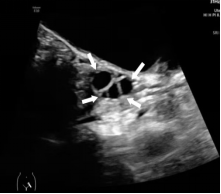

Tanner II期 乳晕后方呈星形或线样低回声区(白色方框)

Tanner III期 腺体组织由乳晕后方向外延伸,中央为蜘蛛状低回声导管区

(白色方框)